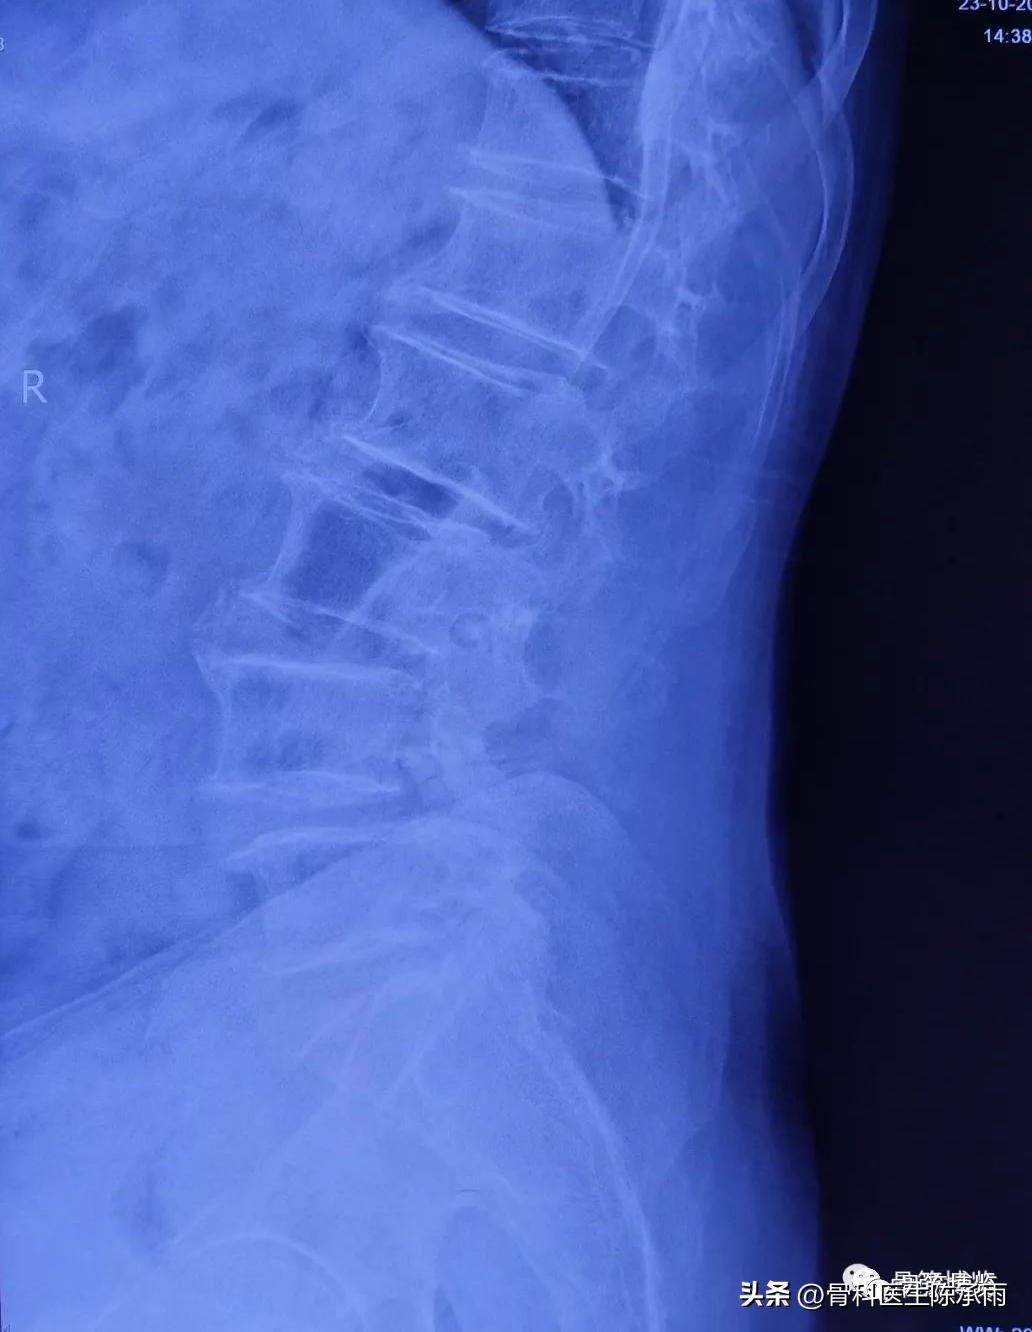

1例 腰椎滑脱伴椎管狭窄

术前影像